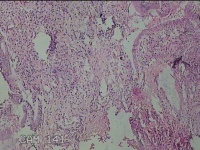

子宫腔内膜

性别

女

年龄

49岁

临床诊断

一般病史

阴道流血16天。

标本名称

大体所见

灰白暗红色不规则碎组织3x2.5x0.8cm一堆。